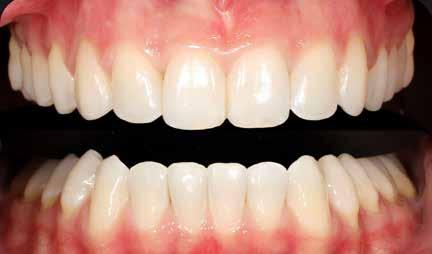

Az esztétikai megjelenés nagyon fontos része a mikroesztétika, azaz a fogak esztétikai formája, arányai, a fogakat összekötő konnektorfelszínek hossza, továbbá az íny lefutása.

A fogak formáját – megfelelő foganyag meglétével – a fogszabályozó kezelés előtt, alatt és után több lépésben elvégzett esztétikai fogkonturálással tudjuk megváltoztatni. Amennyiben nincs megfelelő foganyag a fogszabályozó kezelés

A 28 éves hölgypáciens is elsősorban a szép mosoly elérésének igénye miatt szeretett volna fogszabályozást, bár tudomása volt a mélyharapásáról (1–5. képek).